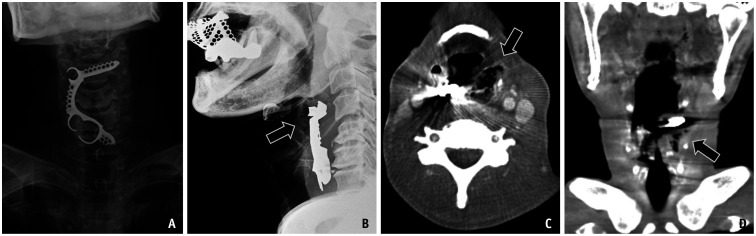

异物摄入和感觉是常见的临床情况遇到急诊和门诊设置。真正的异物摄入通常包括吞咽异物的历史,通常通过x线检查证实。异物摄入的处理取决于异物的类型、大小和位置,以及患者的症状。高风险物体,如钮扣/盘状电池、多个磁铁和尖锐物体,通常需要紧急或紧急内镜切除,以防止穿孔、阻塞和瘘管形成等严重并发症。影像学对诊断和治疗至关重要,x线片是一线方式,CT在检测放射性物体和并发症方面具有卓越的灵敏度。即使没有实际的异物存在,异物摄入和感觉的模拟者也会出现在运动障碍(如贲门失弛缓症)、结构或粘膜异常(如Zenker憩室、反流性食管炎和食管狭窄)和外源性压迫。虽然这些模仿者产生相似的症状,但它们需要不同的诊断方法。本文综述了各种异物的影像学表现、处理策略以及其模仿物的特征,强调了及时准确区分的重要性,以指导适当的干预和改善患者的预后。

Foreign body ingestion and sensation are common clinical conditions encountered in emergency and outpatient settings. True foreign body ingestion typically involves a history of swallowing a foreign object and is often confirmed by radiographic findings. The management of foreign body ingestion depends on the type, size, and location of the object, as well as the patient's symptoms. High-risk objects, such as button/disk batteries, multiple magnets, and sharp objects, often require urgent or emergent endoscopic removal to prevent severe complications such as perforation, obstruction, and fistula formation. Imaging is crucial for diagnosis and management, with radiographs being the first-line modality and CT offering superior sensitivity for detecting radiolucent objects and complications. Mimickers of foreign body ingestion and sensations, even without the presence of an actual foreign body, arise from motility disorders (e.g., achalasia), structural or mucosal abnormalities (e.g., Zenker's diverticulum, reflux esophagitis, and esophageal strictures), and extrinsic compression. Although these mimickers produce similar symptoms, they require different diagnostic approaches. This review highlights the radiological findings, management strategies for various foreign bodies, and the distinguishing features of their mimickers, emphasizing the importance of timely and accurate differentiation to guide appropriate interventions and improve patient outcomes.